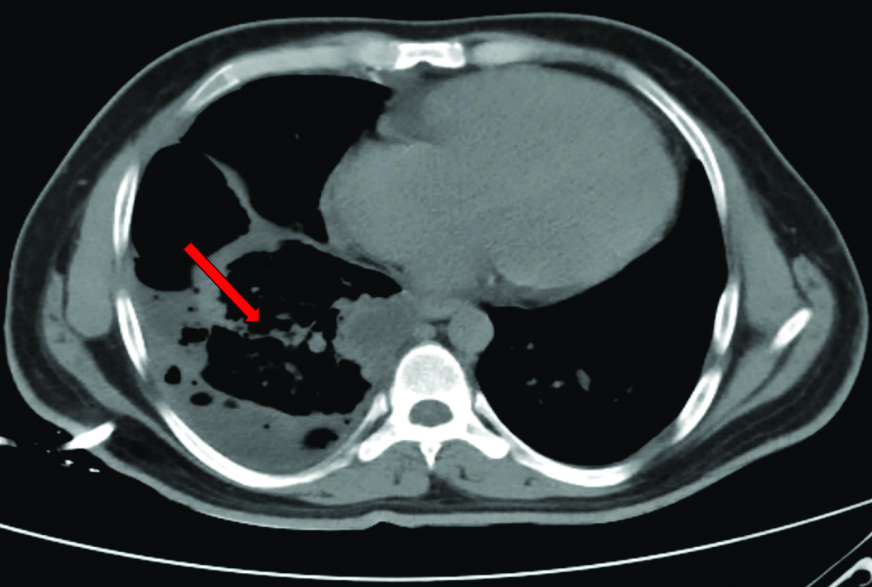

The patient was diagnosed with right loculated pleural effusion-haemothorax and congenital heart disease with Eisenmenger syndrome. Initial management included the insertion of a right-sided 14 F pigtail catheter, intravenous antibiotics, adequate analgesia and oxygen therapy. However, the initial drainage post-pigtail insertion was minimal (100 mL) [Table/Fig-5]. Due to the lack of subsequent drainage, even after reconfirming the tube position and patience, the patient was administered IPFT with 2.5 lac IU STK. The first cycle of IPFT resulted in 1150 mL of drainage, with a cumulative drainage of 2250 mL after three days [Table/Fig-6,7].

CT thorax showing resolution of effusion (red arrow) post Intrapleural Fibrinolytic Therapy (IPFT).

After confirming resolution on serial chest radiography, the intercostal drainage was removed and the patient was followed-up in the outpatient unit. No recurrence of pleural effusion was noted in subsequent chest radiographies [Table/Fig-8].